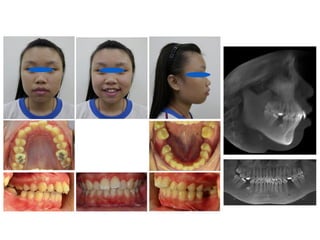

Mouth breathing - adenoid face

 Long and narrow head

 Dental Malocclusion

 Droopy lower lip

 Upper lip that is shorter then

normal

 Gummy smile

 Flattened cheek

 Dark Circles Under Eyes

790516

810410

蕭郁庭